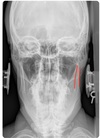

AP LOWER CERVICAL LANDMARKS

c3-t2 vertebral bodies

73

A-P lower cervical view

uncinate processes c3-c7

74

articular pillars

75

TVP's of cervical + thoracic spine

76

SP's of c2-t12

77

clavicles

78

angle of mandible

79

base of occiput

80

pedicles of c1-t12

81

ribs

82

tracheal air shadow